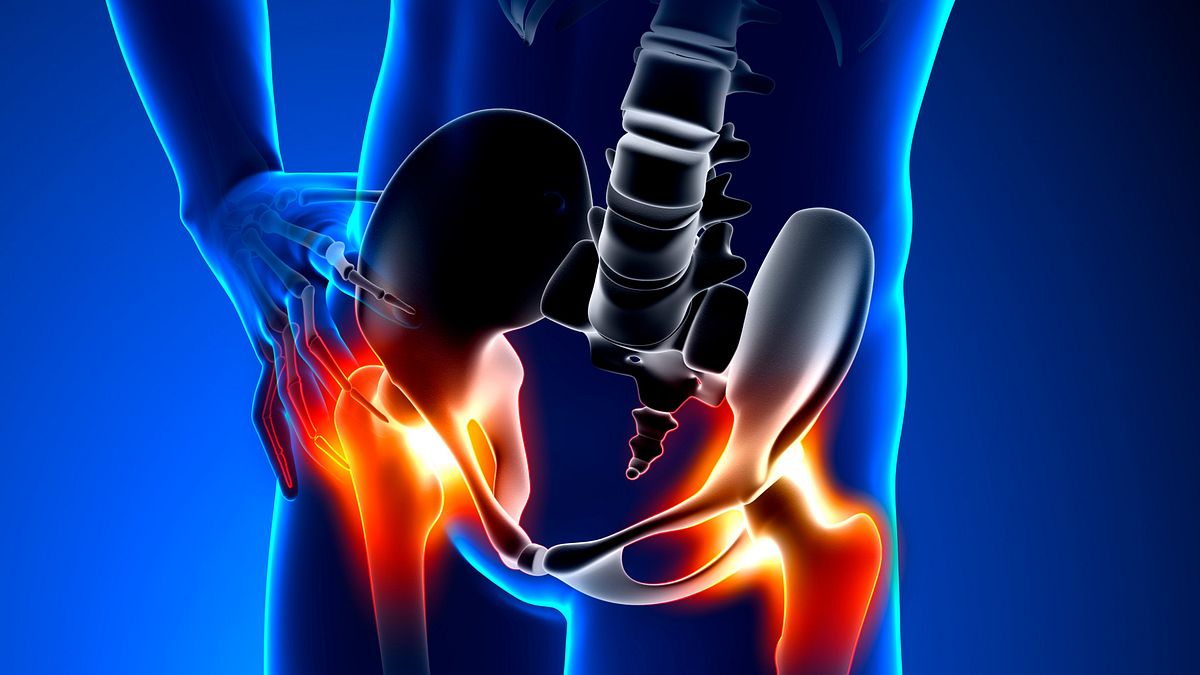

Hip Pain